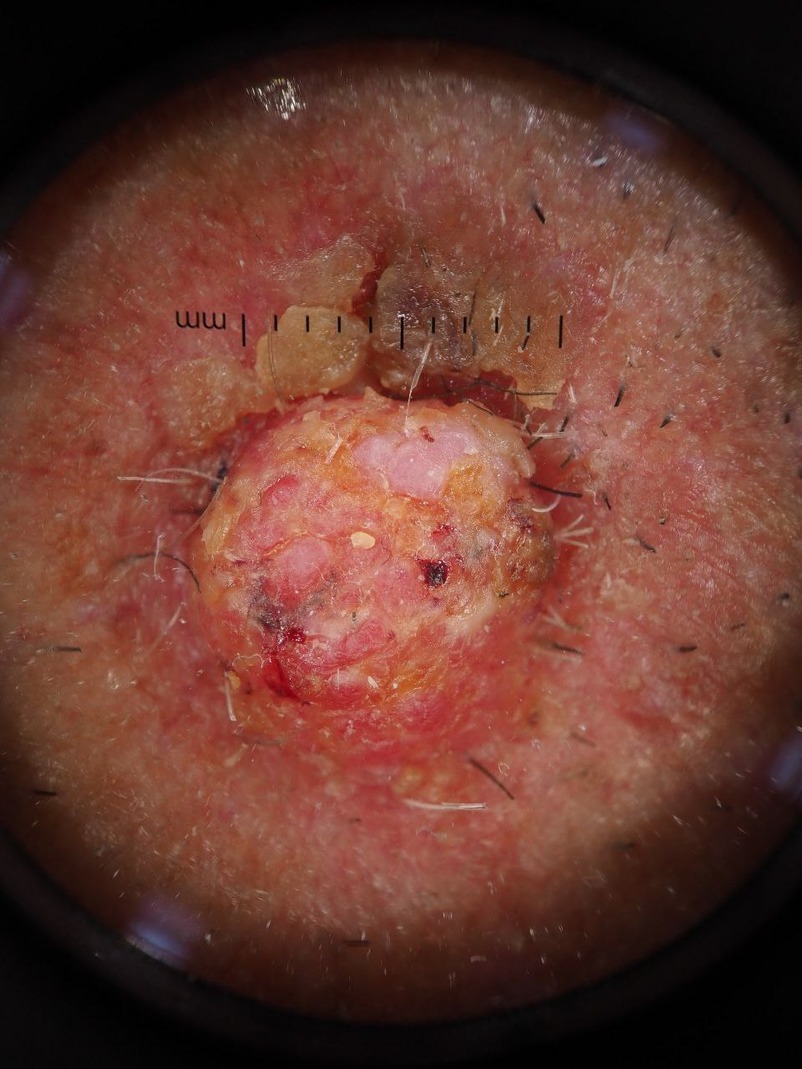

Paramount Skin Check offers professional, in-person skin assessments using advanced imaging technology to detect early signs of skin cancer and other skin conditions. Simply book an appointment, visit our partner setting, and let our trained team capture high-quality images of your skin concern. Each case is reviewed by a fully licensed consultant dermatologist, ensuring that your results are based on expert clinical judgment—not just algorithms. While some services rely solely on AI, we believe that early detection requires the eyes and experience of real specialists who understand the subtle warning signs that machines may miss. Within 48 hours, you'll receive an advice letter to help fast-track your referral into the NHS pathway. No waiting lists, no guesswork—just trusted answers and peace of mind. Paramount Skin Check: real experts, real care, right when you need it.